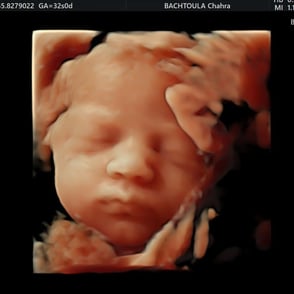

L'échographie du 3e trimestre (entre 32 et 34 SA) nous permet de refaire un examen morphologique du bébé, d'apprécier sa croissance et de vérifier sa position avant l'accouchement.

Galerie des clichés d'échographie